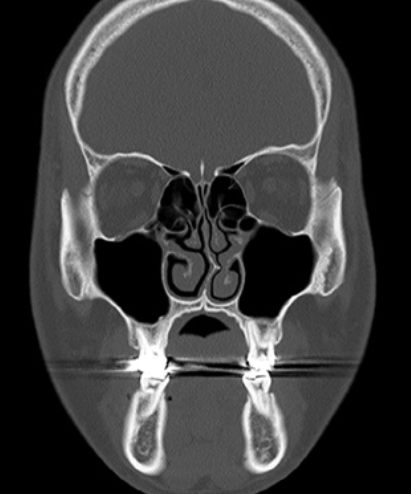

4. 비중격 만곡의 진단

비중격 만곡은 코 안을 진찰하여 간단하게 진단할 수 있습니다.

이와 동반된 질환을 찾아내기 위하여 내시경 검사, 방사선 검사, 혈액 검사 등을 시행할 수 있습니다.